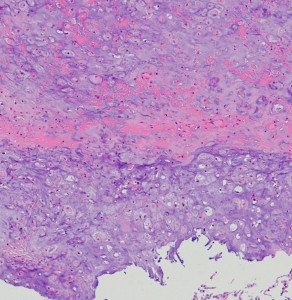

低悪性度軟骨肉腫の病理像 grade 2 chondrosarcoma

背景は好塩基性の軟骨基質(粘液状 myxoid,軟骨様 chondroid)です。好酸性胞体をもつ異型紡錘形ないし上皮様細胞が多結節状に増殖しています。細胞密度はやや高い部分もあり,核は濃縮され大小不同や2核の細胞も見られます。MIB-1 index 3%